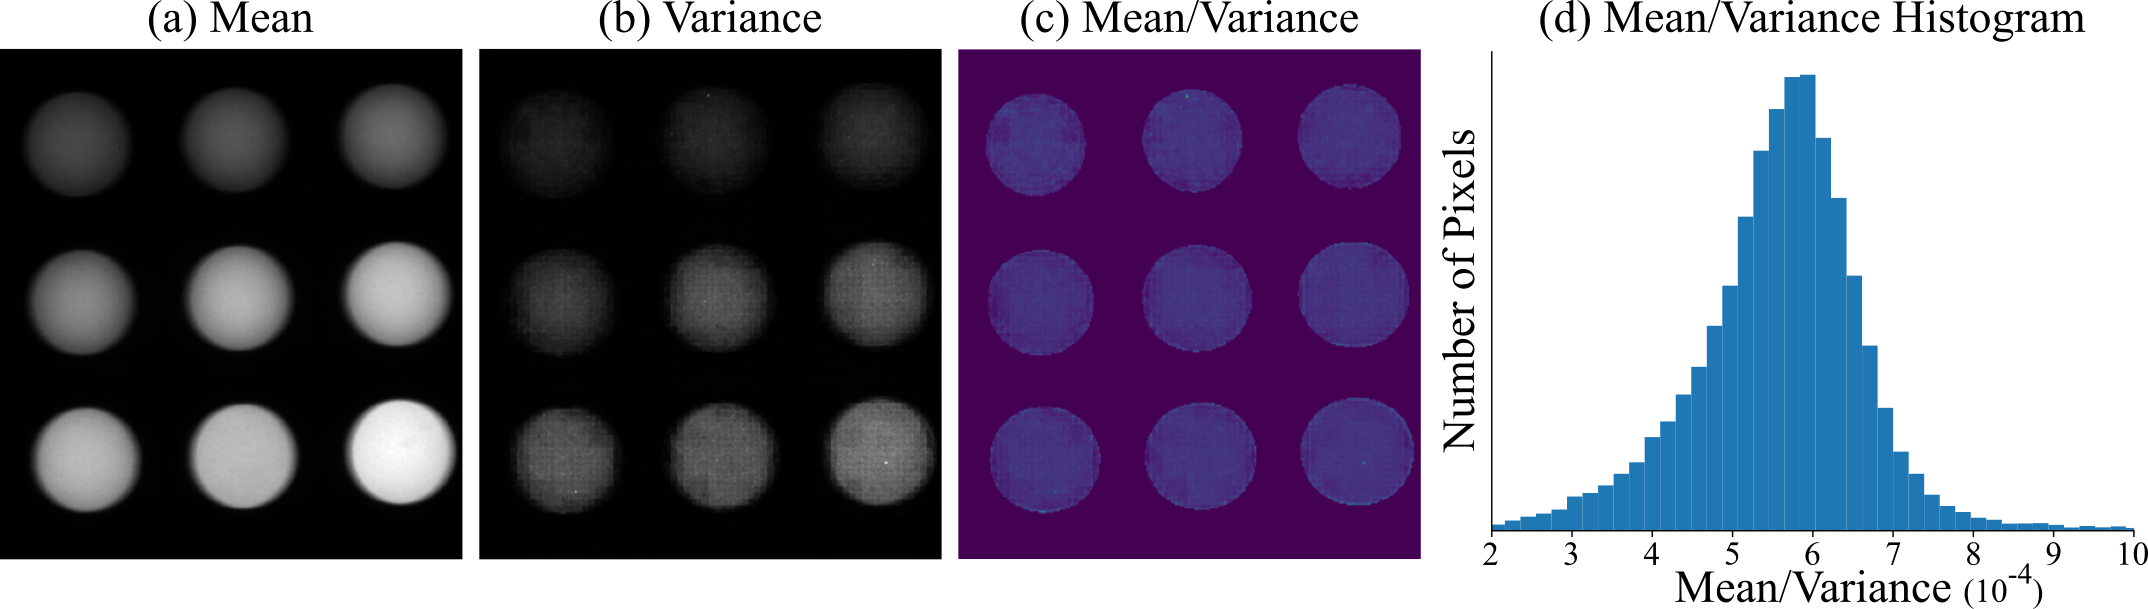

• OL-Phantom contains 1,830 frames (90 seconds) of a Quel phantom (RCS-ICG-ST01-QUEL03) [13] for camera gain calibration. A fluorescence phantom is designed to mimic fluorescence properties of a contrast agent and acts as a fluorescent standard. The Quel phantom is a 3 by 3 grid of calibrated phantom wells of varying concentrations that is used for calibration and testing of FGS systems.

In order to calibrate our noise model to a specific commercial camera we use OL-Calibration. We solve for the gain K𝐾Kitalic_K of our camera using OL-Phantom and the fact that the Poisson distribution will have mean equal to variance. We find the K𝐾Kitalic_K value that best fits a Poisson distribution over all Quel phantom wells, see supplement for details. Next we simulate Rtsubscript𝑅𝑡R_{t}italic_R start_POSTSUBSCRIPT italic_t end_POSTSUBSCRIPT by randomly sampling time-contiguous dark frames from OL-Dark which recent work [21] has shown to be more accurate than the common Gaussian random variable or other physics based models for read noise. Next, we use a low noise FV from OL-Combined for Stsubscript𝑆𝑡S_{t}italic_S start_POSTSUBSCRIPT italic_t end_POSTSUBSCRIPT, and find an estimate for LtLLsubscriptsuperscript𝐿𝐿𝐿𝑡L^{LL}_{t}italic_L start_POSTSUPERSCRIPT italic_L italic_L end_POSTSUPERSCRIPT start_POSTSUBSCRIPT italic_t end_POSTSUBSCRIPT using our LLL-PN. In Fig. 3, we show images from OL-Real as well as our simulated data with varying Smsubscript𝑆𝑚S_{m}italic_S start_POSTSUBSCRIPT italic_m end_POSTSUBSCRIPT and Lmsubscript𝐿𝑚L_{m}italic_L start_POSTSUBSCRIPT italic_m end_POSTSUBSCRIPT levels. Notice as Lmsubscript𝐿𝑚L_{m}italic_L start_POSTSUBSCRIPT italic_m end_POSTSUBSCRIPT increases non-fluorescent objects begin to appear in F~tvsubscriptsuperscript~𝐹𝑣𝑡\tilde{F}^{v}_{t}over~ start_ARG italic_F end_ARG start_POSTSUPERSCRIPT italic_v end_POSTSUPERSCRIPT start_POSTSUBSCRIPT italic_t end_POSTSUBSCRIPT; for example, hands are a good sign of significant LLL, but also generally the signal is obscured by LLL from tissue.